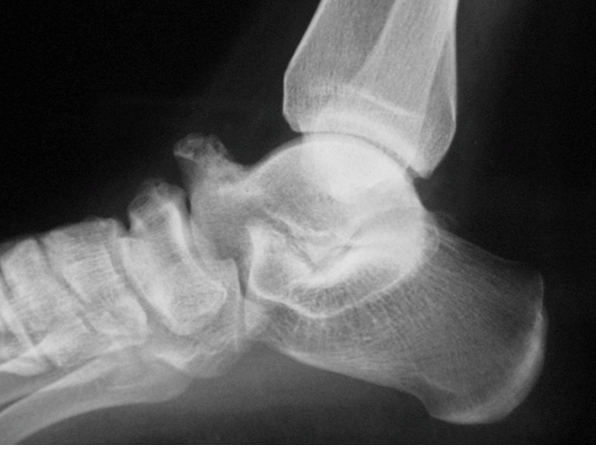

Dalla Rx il piede destro mostrava un segno C e un prominente becco talare coerente con la coalizione tarsale. Inizialmente il paziente è stato trattato con riduzione dell’attività, riposo e analgesici per 6 settimane. Tuttavia, non ha risposto positivamente al trattamento conservativo. La risonanza magnetica è stata eseguita per delineare altre possibili cause di dolore persistente alla caviglia. In questo caso, si è deciso di procedere per via chirurgica, il talar beak e la borsa sono stati rimossi con chirurgia a cielo aperto.

Fig. 1 Le semplici radiografie del piede destro mostravano un segno C continuo e un prominente becco talare